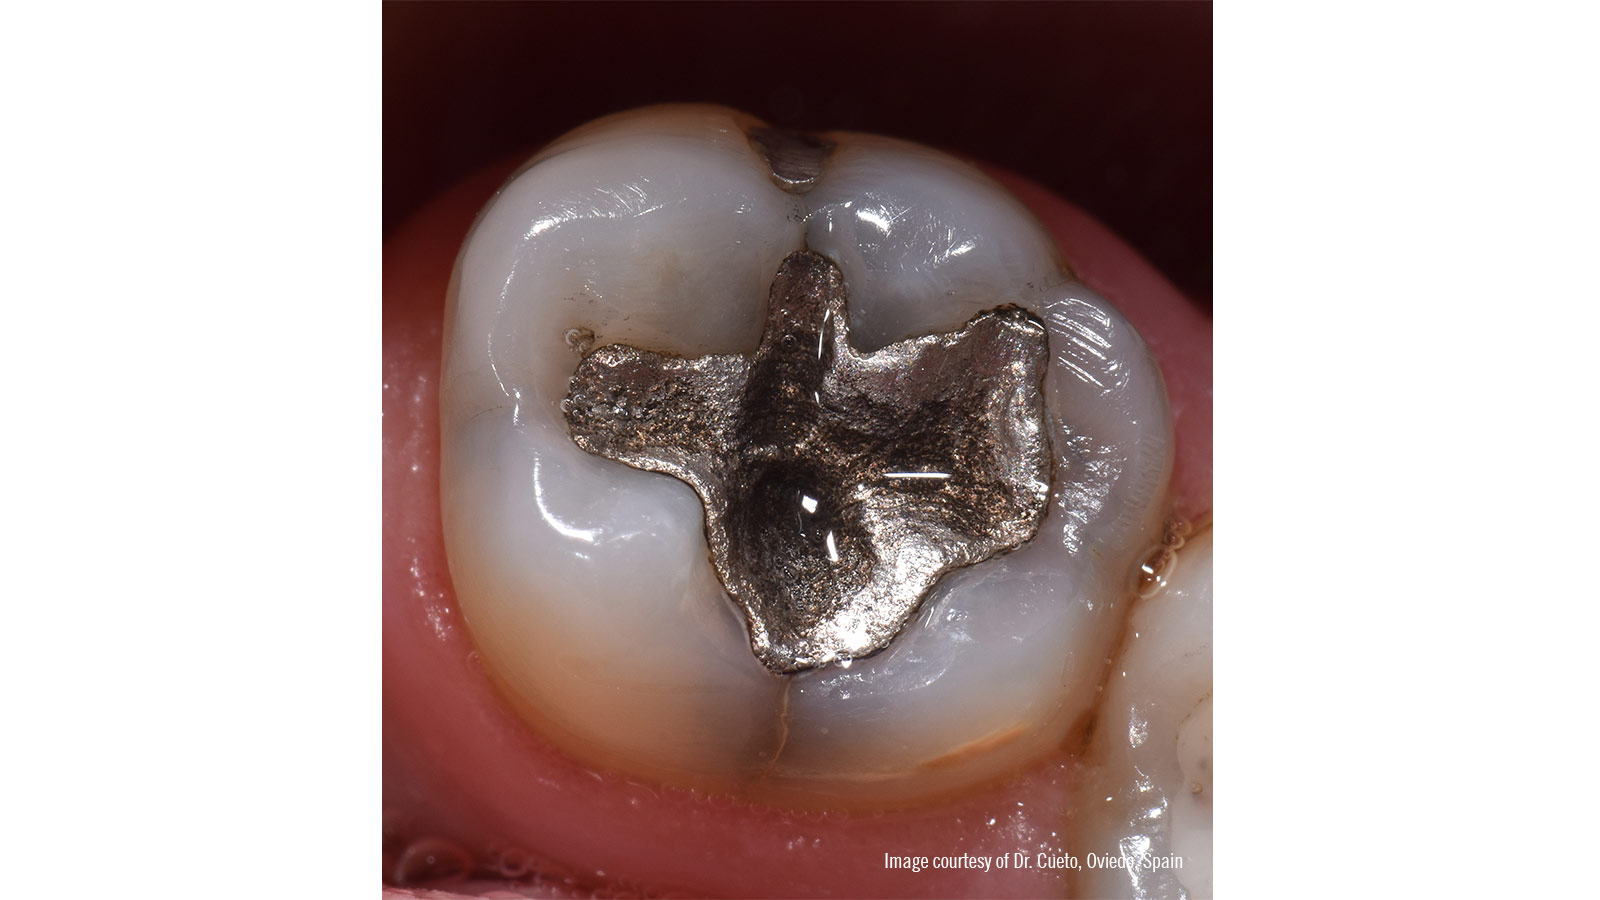

Vervanging van een oude amalgaamrestauratie met Venus Pearl ONE en Venus Bulk Flow ONE van Kulzer

amalgam restoratio

Deze eerste kies linksonder (36) heeft al jaren een amalgaamrestauratie, met marginale openingen en haarscheurtjes rondom het vulmateriaal.

removed with burs

Na plaatsing van de rubberdam werd de amalgaamrestauratie verwijderd met boren en waterkoeling. De caviteit vertoont zichtbare secundaire cariës.